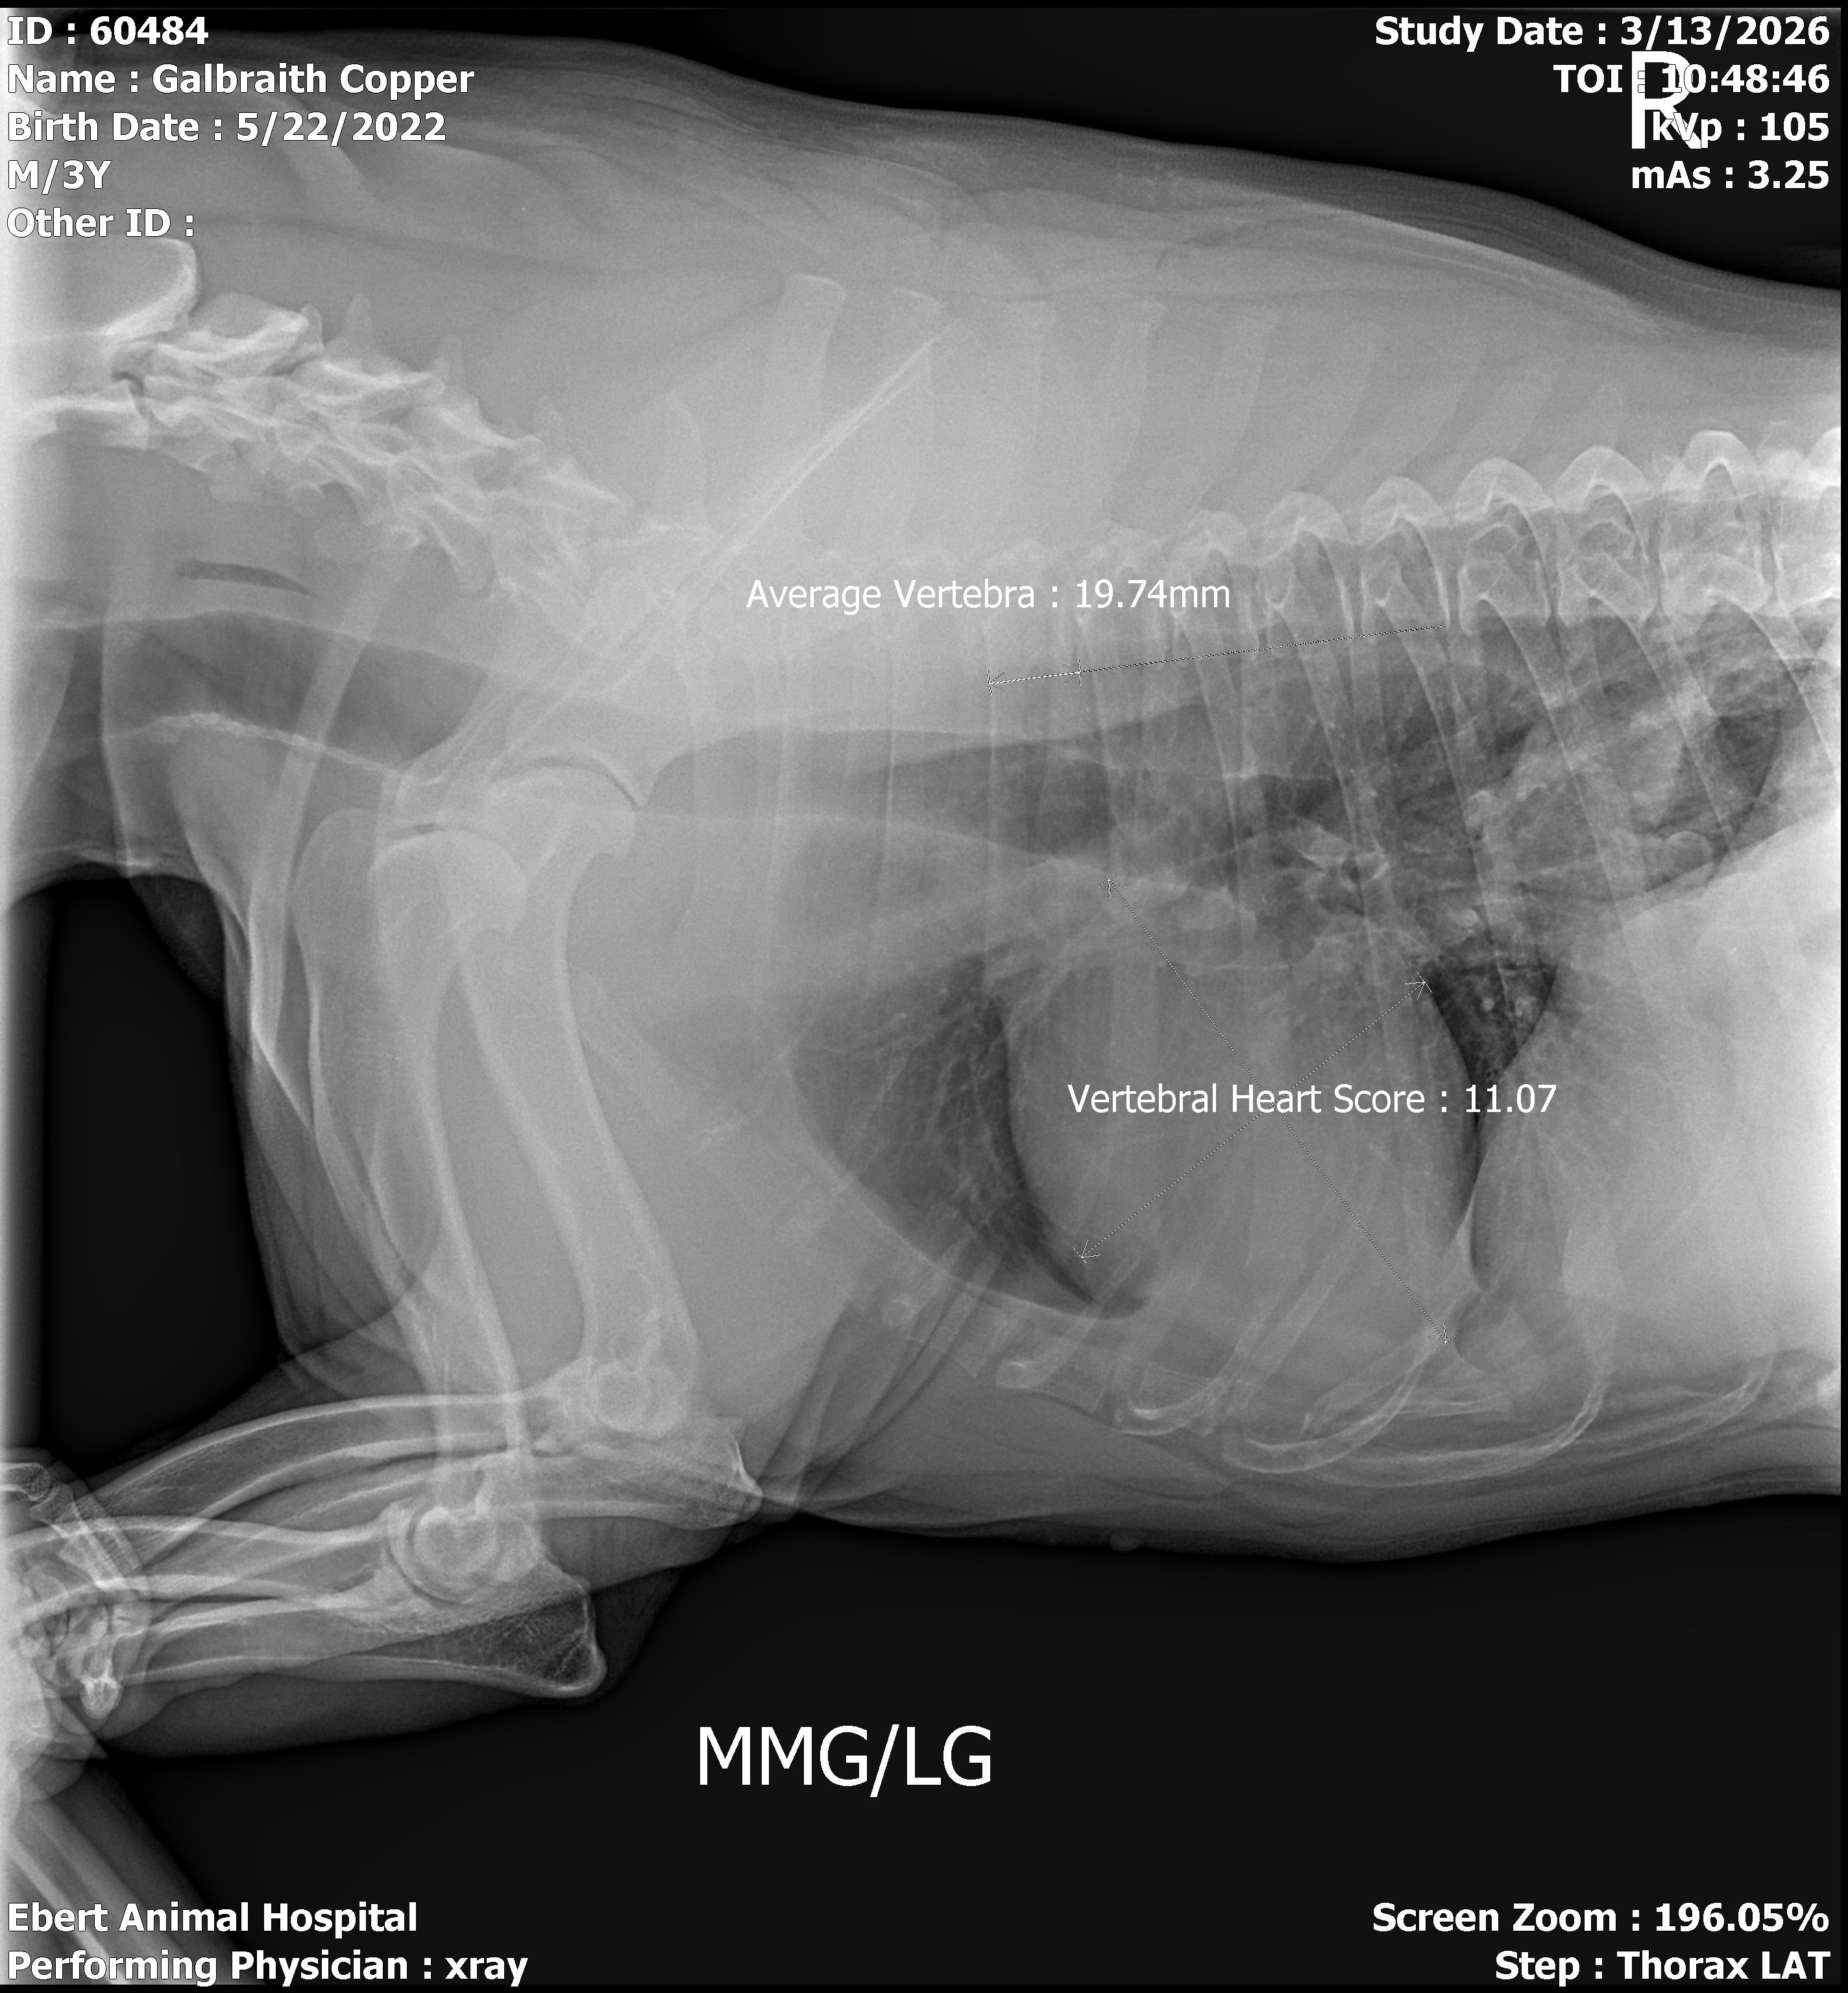

Hello, my name is June Galbraith. I am starting this for the second time because the first time didn't get enough $. This is to raise $ to cover the cost of my dog Copper's surgery. He has something stuck in his esophagus. Pet insurance doesn't pay till after we pay. So here we go. I hate doing this because I'm not one to ask for help, especially a second time. Yes, I had a GoFundMe but only raised $225.00. We need $4000. Copper is considered the neighborhood's dog. He stops to see anyone. We were very blessed to get him. Thank you for your generosity. God bless all of you for your help and prayers.